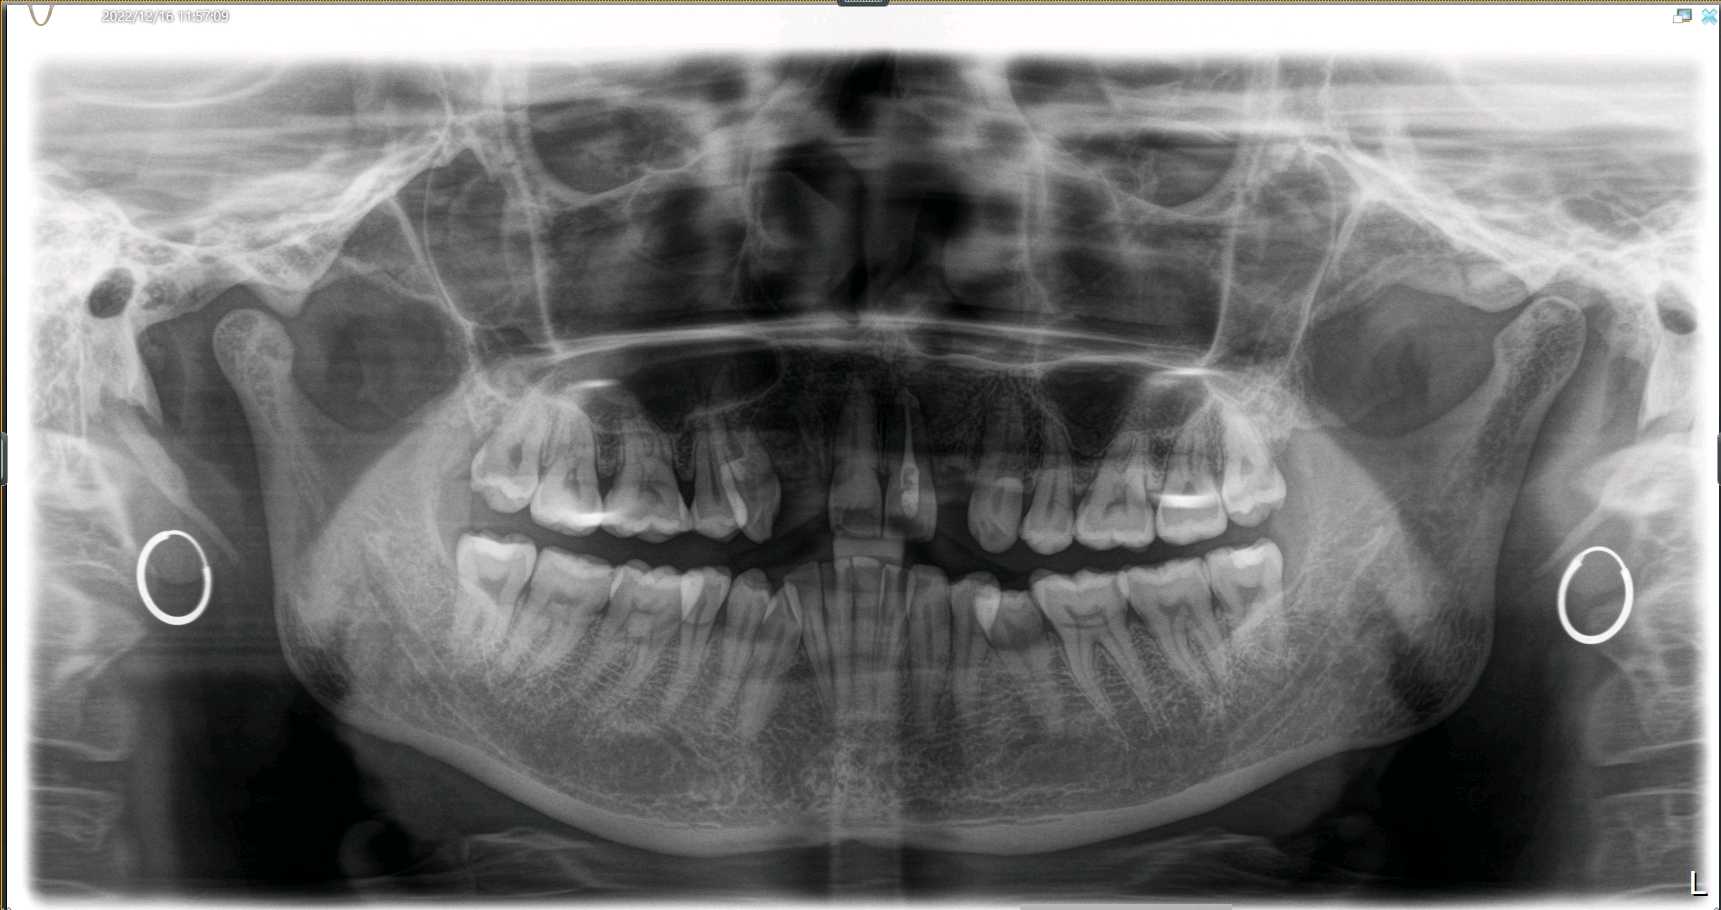

患者女40岁,12、22缺失,拔牙窝凹陷,牙龈乳头形态正常,近远中径较宽;唇侧龈缘曲线良好,与邻牙基本协调 。CBCT示:唇侧骨板不完整,牙长轴与上颌骨长轴平行。

术前